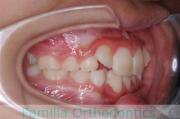

歯並びを治したいということで来院されました。下あごがやや右側に偏位して後退している、上顎前突(出っ歯)でした。上下左右から小臼歯を抜歯して、歯科矯正用アンカースクリューを併用したマルチブラケット法にて治療を行いました。約2年、24回の来院をしていただきました。

下顎の後退はいびきなどの上部気道の障害が出やすいと考えられます。